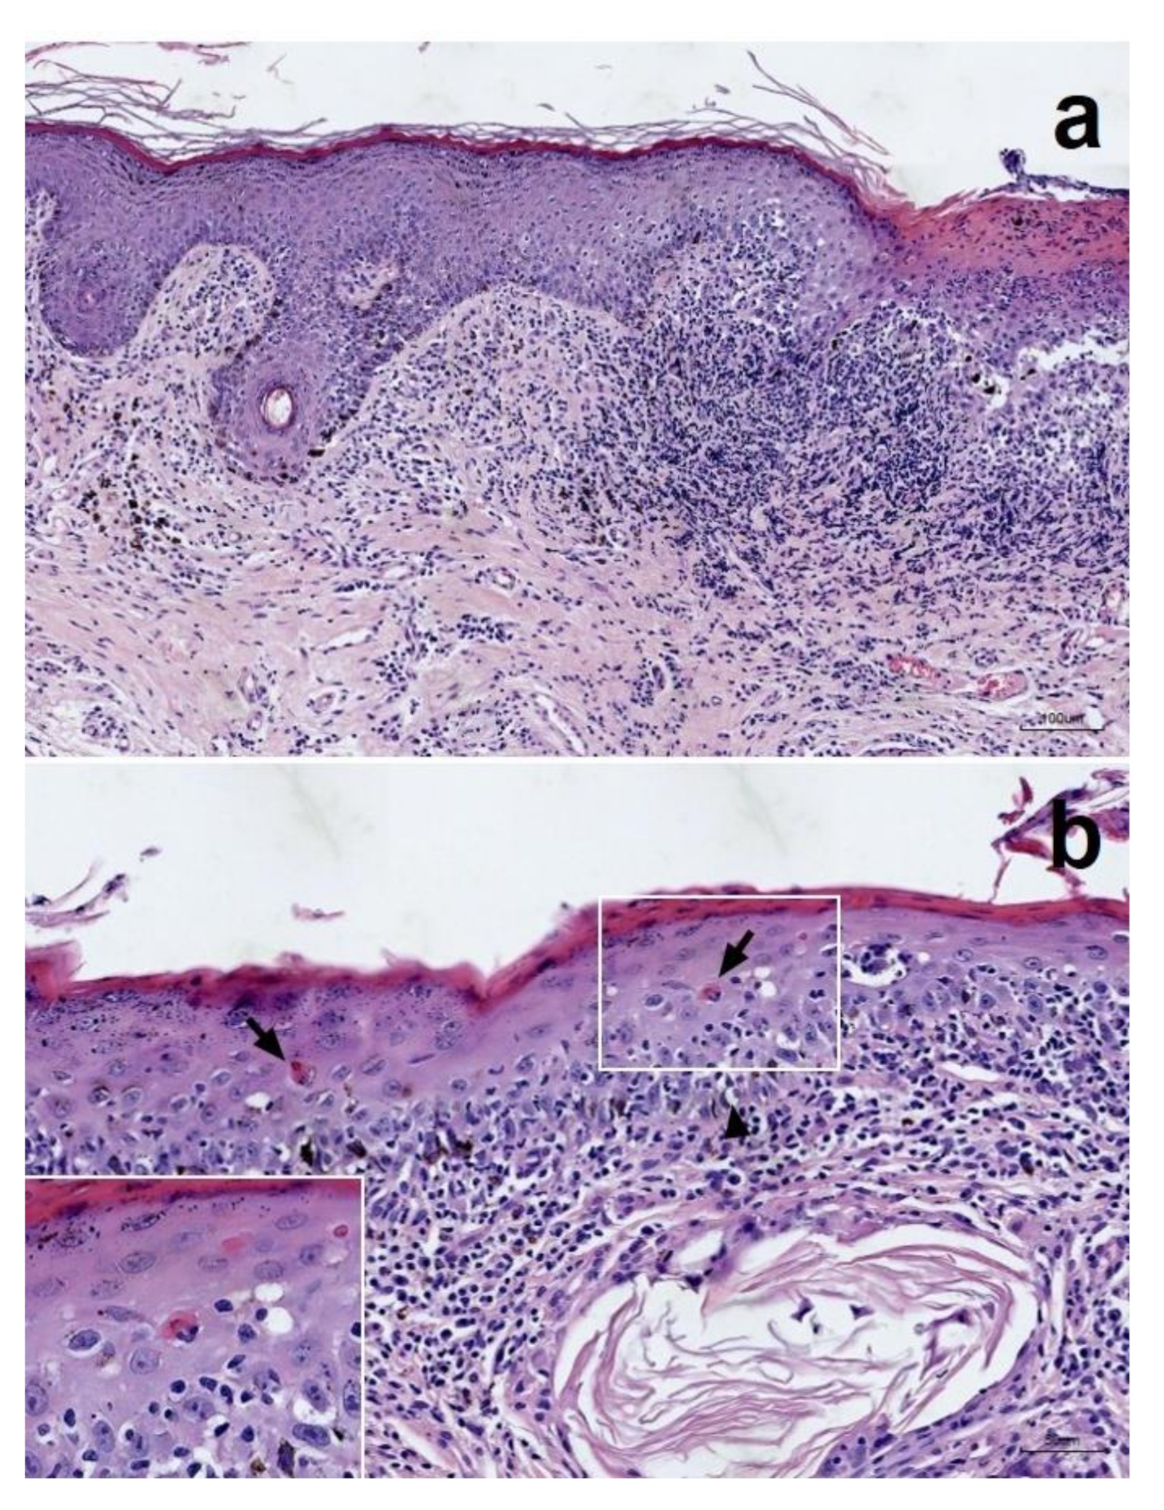

Successful Treatment of Mucocutaneous Lupus Erythematosus in a Dog with Prednisolone, Mycophenolate Mofetil and Tacrolimus

2. Case History